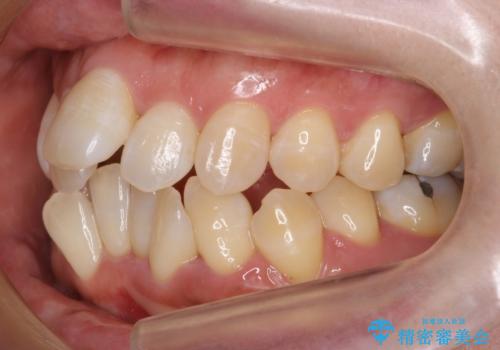

- 前歯の重なりを主訴に来院。

前歯が顔の真ん中に飛び出しているような状態でした。

右上の犬歯が奥深く埋伏していました。

右上以外の3本を抜歯しきちんと並べました。

成人の矯正でしたので、矯正治療前にしっかり必要な歯周病治療を行い、状態が改善してから開始しました。